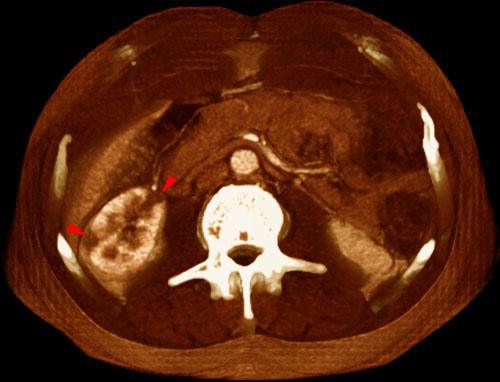

Infarto renal segmentario